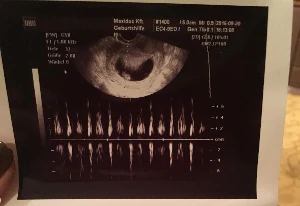

Terhesnapló10 - Liza: Rákos vagyok. Na és?! (10. hét)